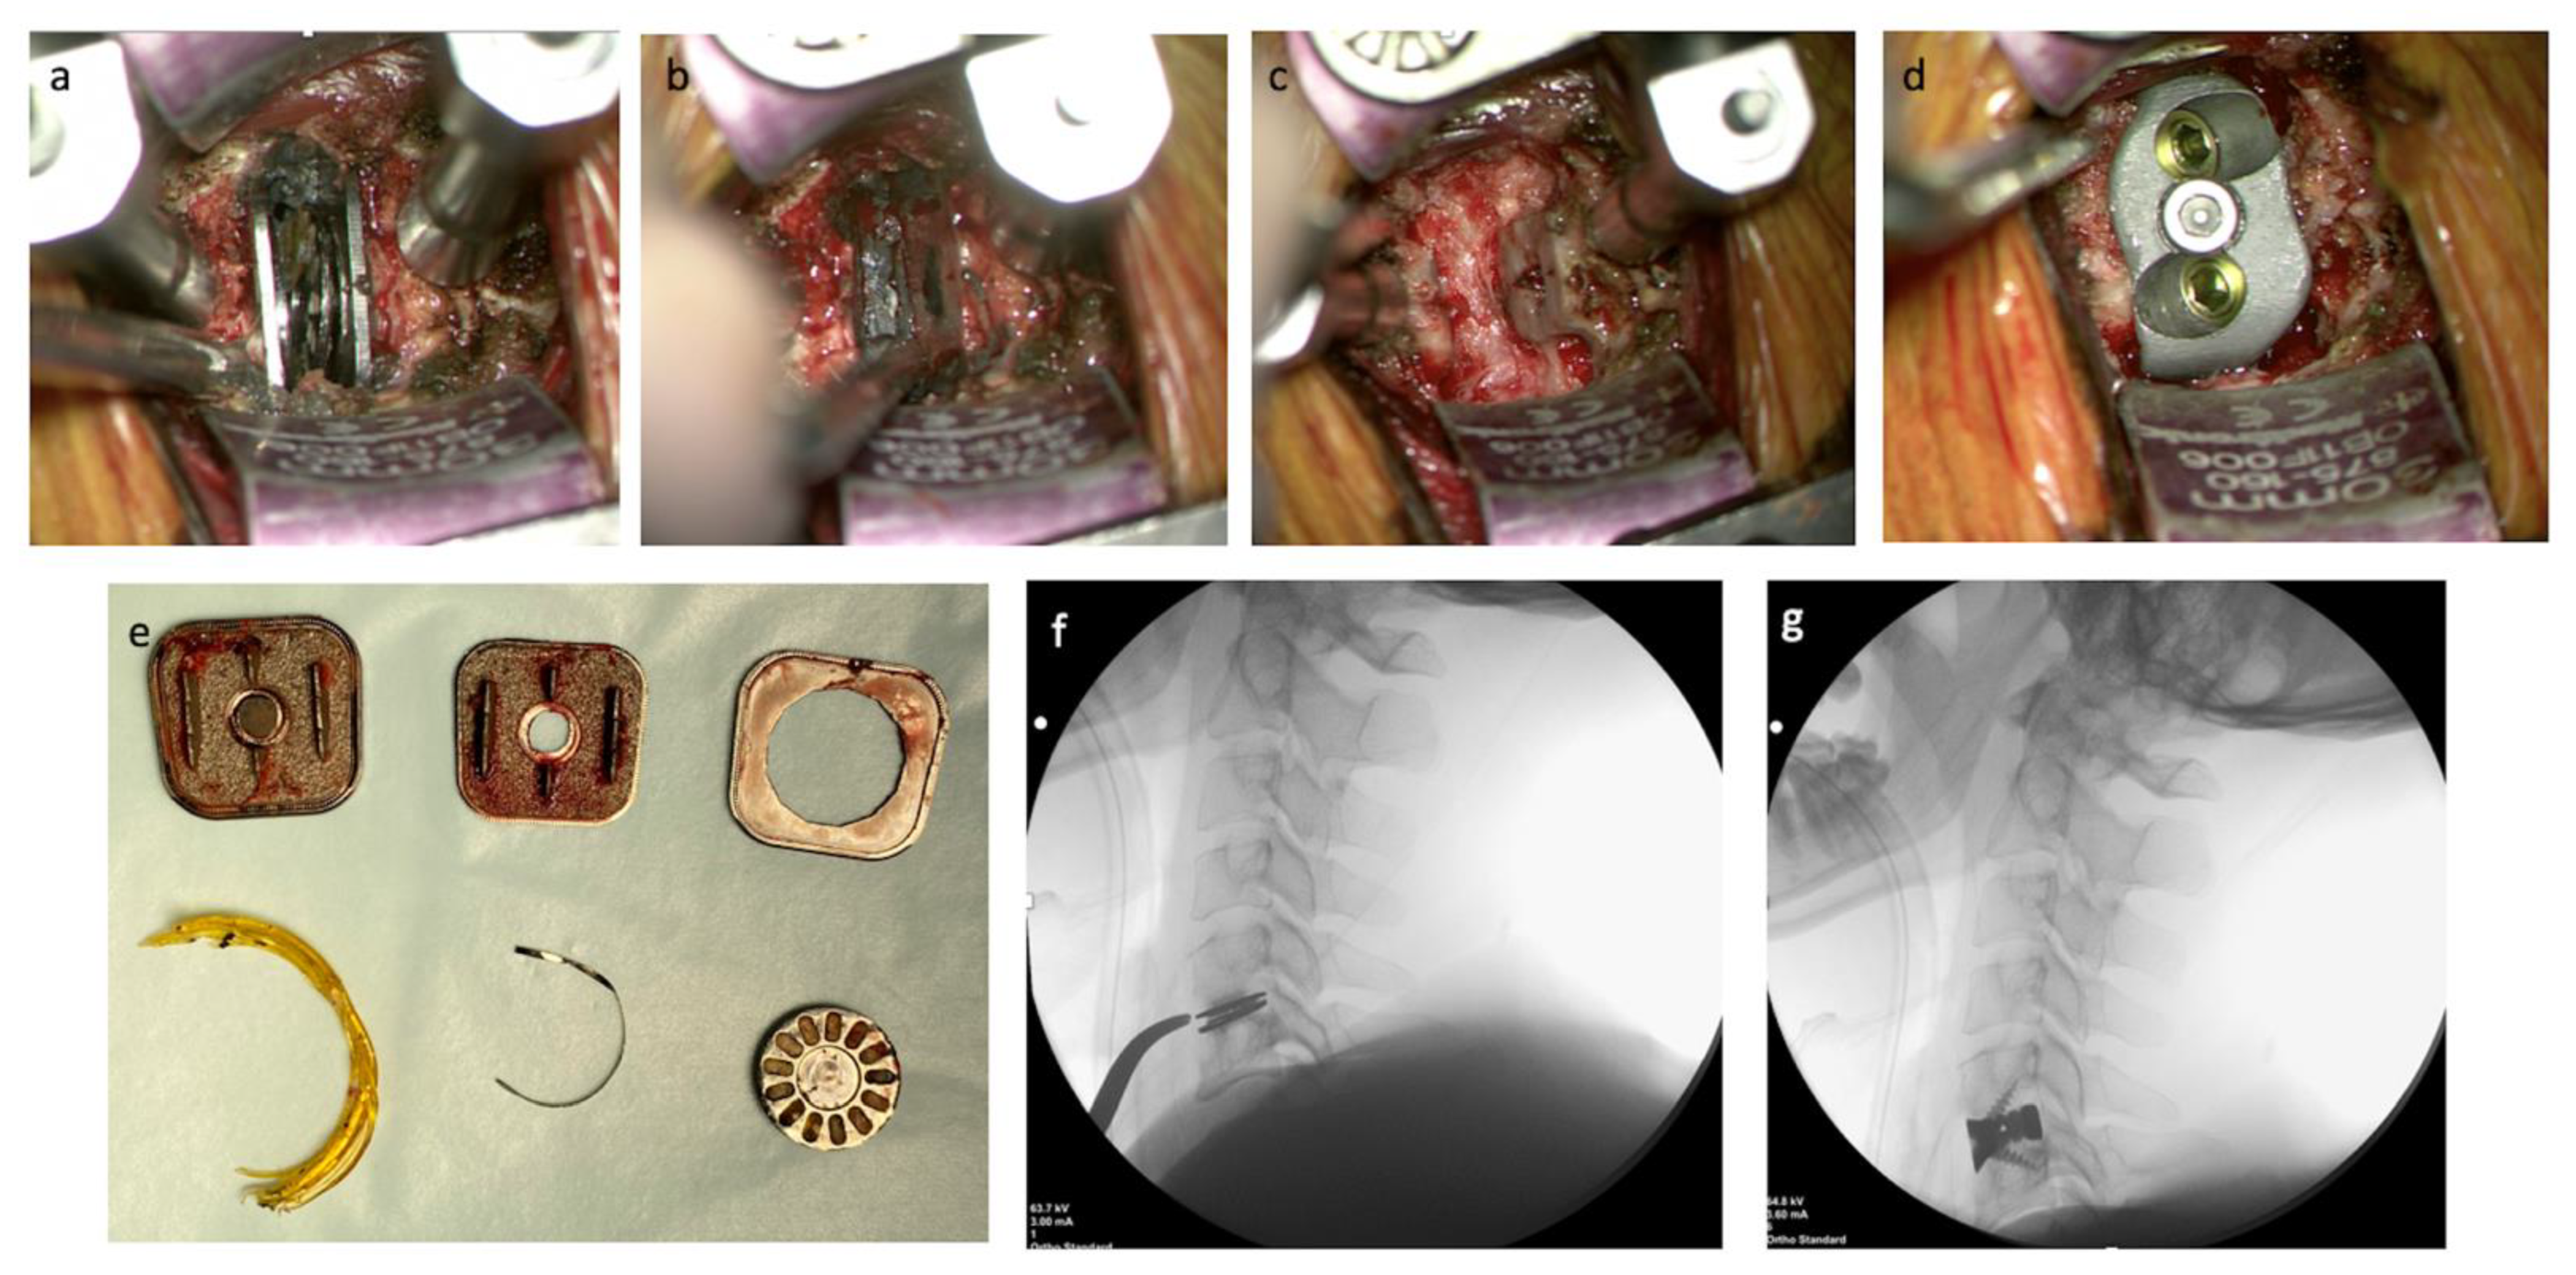

2.3. Operative Technique